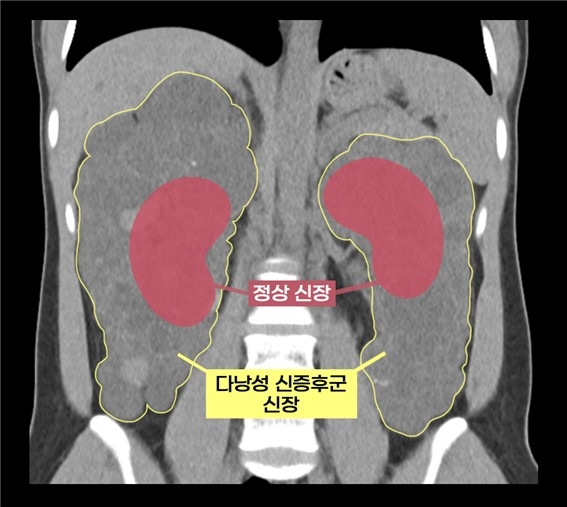

다낭성 신증후군은 신장에 수많은 낭종이 발생해 신장이 최대 축구공 크기만큼 커지는 유전질환으로, 1천 명 중 한 명꼴로 발병한다. 대개 만성 신부전으로 이어진다.